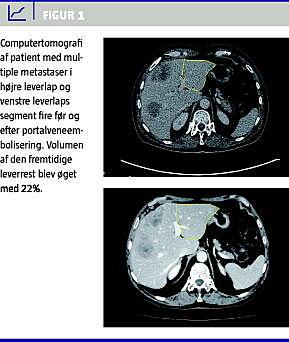

Leverresektion anses indtil videre for at være den mest effektive behandling af kolorektale levermetastaser. En forudsætning for langtidsoverlevelse er, at der opnås en R0-resektion (makro- og mikroradikal). Metastaser fra kolorektal cancer er langt den hyppigste indikation for leverkirurgi [1]. Desværre er kun 10-15% af patienterne tilgængelige for leverkirurgi på diagnosetidspunktet. I de seneste årtier er der sket et paradigmeskift i opfattelsen af, hvornår levermetastaser er resektable. Patienter med flere end tre metastaser, bilobære metastaser, lymfeknudemetastaser i leverhilus, lungemetastaser eller en mulig kirurgisk margin på < 1 cm blev ofte betragtet som ikkeresektable. Nu fokuseres der ikke længere på, hvad der kan fjernes, men hvad der er tilbage efter resektionen. Kan der opnås en R0-resektion (for hepatisk og ekstrahepatisk sygdom) med samtidig bevarelse af sufficient volumen af den fremtidige leverrest (~ 20-30% af det totale levervolumen), betragtes patienten som resektabel. Det er derfor muligt at øge resektabiliteten hos primært ikkeresektable patienter, hvis metastaserne kan gøres mindre, eller volumen af den fremtidige leverrest kan øges. Med moderne kombinationskemoterapi synes det muligt at reducere metastasernes størrelse, så op mod 35% af de primært ikkeresektable patienter bliver tilgængelige for leverresektion uden øget operativ risiko og med en treårsoverlevelse på 73% [2]. Volumen af den fremtidige leverrest kan øges ved portalveneembolisering (PVE). Oftest emboliseres den højre portalgren +/− segmentfire-grenene, for at få segment to og tre i venstre leverlap til at hypertrofiere (Figur 1 ). PVE øger volumen af den fremtidige leverrest med ca. 9-15%, hvilket muliggør ekstensive resektioner. Patienter med multiple bilobære metastaser har mulighed for kurativ resektion ved såkaldt two-stage -resektion. Ved den første operation foretages leverbesparende lokal resektion eller radiofrekvensablation (RFA) af metastaserne i den fremtidige leverrest (typisk segment to og tre), der suppleres enten med peroperativ ligering af den højre portalvene eller postoperativ transhepatisk PVE. Ca. seks uger efter foretages fornyet computertomografi eller magnetisk resonans-skanning for at vurdere resekatabiliteten. Er R0-resektion mulig med sufficient volumen af den fremtidige leverrest, fortsættes med den anden operation. Her fjernes de resterende metastaser med en højresidig eller udvidet højresidig hemihepatektomi. I perioden mellem de to operationer kan der gives kemoterapi, uden at det påvirker hypertrofien af den fremtidige leverrest. Two-stage -resektion kan opnås hos ca. 75% af patienterne, uden perioperativ mortalitet og med en femårsoverlevelse på 50% [3].